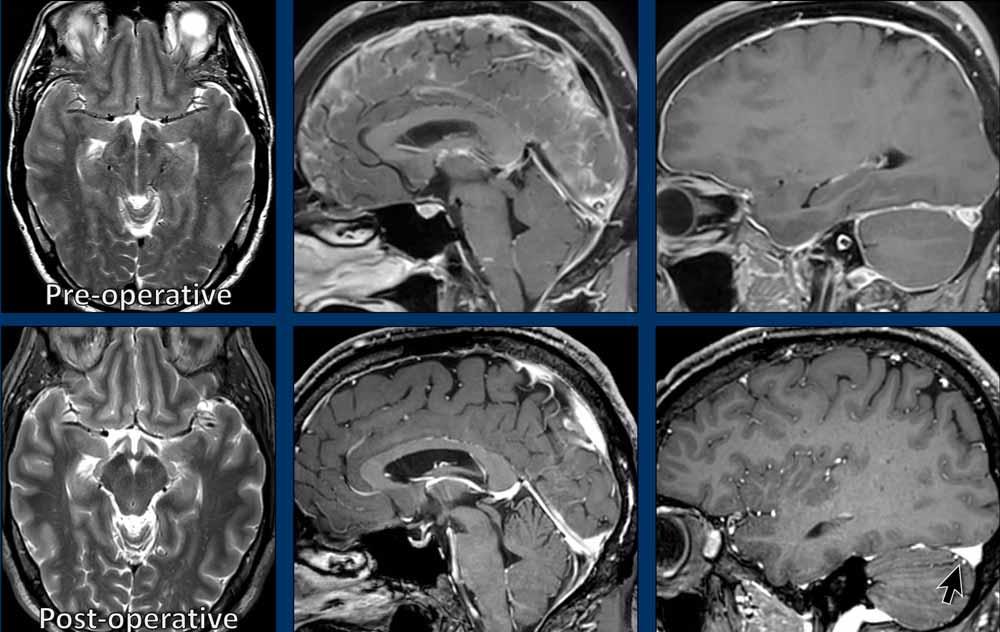

So sánh các hình ảnh trước phẫu thuật với các hình ảnh sau phẫu thuật.

Lưu ý sự trở về bình thường của các dấu hiệu hình ảnh.

Quan trọng nhất, các cơn đau đầu đã biến mất.

Cả hai bệnh nhân đều là phụ nữ trẻ với đau đầu mạn tính.

Bệnh nhân nào mắc SIH và bệnh nhân nào mắc CM1?

Hình ảnh

- Hạnh nhân tiểu não tụt thấp

Dấu hiệu không thật sự rõ ràng, một phần do có xảo ảnh chuyển động, nhưng hình dạng thân não không bình thường và có vẻ khoảng cách giữa cầu não và thể vú bị rút ngắn.

Có thể cũng có một số dấu hiệu ứ trệ tĩnh mạch. - Ngoài hạnh nhân tiểu não tụt thấp, hình ảnh trông bình thường.

Tiếp tục với các hình ảnh bổ sung……

- Bốn hình ảnh bên trái cho thấy các dấu hiệu điển hình của SIH với bờ lồi của xoang ngang, khoảng cách ngắn giữa thể vú và cầu não, và hình ảnh trung não bị võng xuống.

- Các hình ảnh bên phải không cho thấy các dấu hiệu này.

Bệnh nhân SIH đã được điều trị bốn lần bằng vá máu mù và đạt kết quả thành công.

Bệnh nhân Chiari type I đã được phẫu thuật giải ép vùng sọ-cổ và đạt kết quả tốt.

Đây là trách nhiệm của chúng ta với tư cách là bác sĩ chẩn đoán hình ảnh: giúp bệnh nhân SIH tránh khỏi việc bị điều trị nhầm như bệnh nhân Chiari type I.